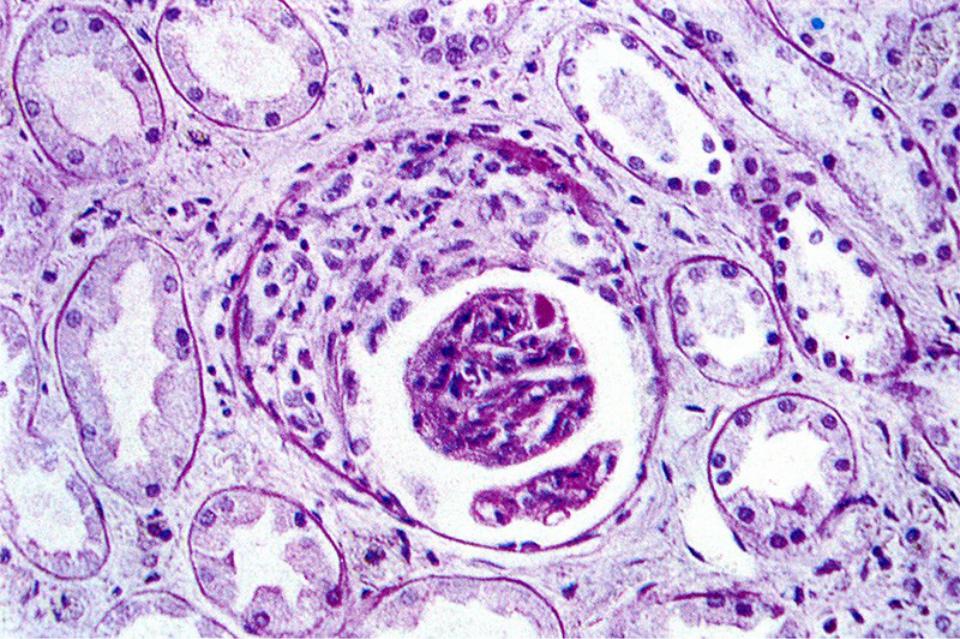

Симптомы подострого гломерулонефрита: фото и описание

Раздел: Визуальный дайджест